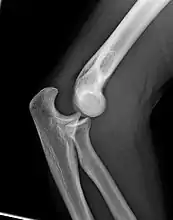

Right: AP X ray of a dislocated right elbow

The types of disease most commonly seen at the elbow are due to injury.

Fractures

There are three bones at the elbow joint, and any combination of these bones may be involved in a fracture of the elbow. Patients who are able to fully extend their arm at the elbow are unlikely to have a fracture (98% certainty) and an X-ray is not required as long as an olecranon fracture is ruled out.[27] Acute fractures may not be easily visible on X-ray.[28]

Dislocation

Elbow dislocations constitute 10% to 25% of all injuries to the elbow. The elbow is one of the most commonly dislocated joints in the body, with an average annual incidence of acute dislocation of 6 per 100,000 persons.[30] Among injuries to the upper extremity, dislocation of the elbow is second only to a dislocated shoulder. A full dislocation of the elbow will require expert medical attention to re-align, and recovery can take approximately 8–14 weeks.